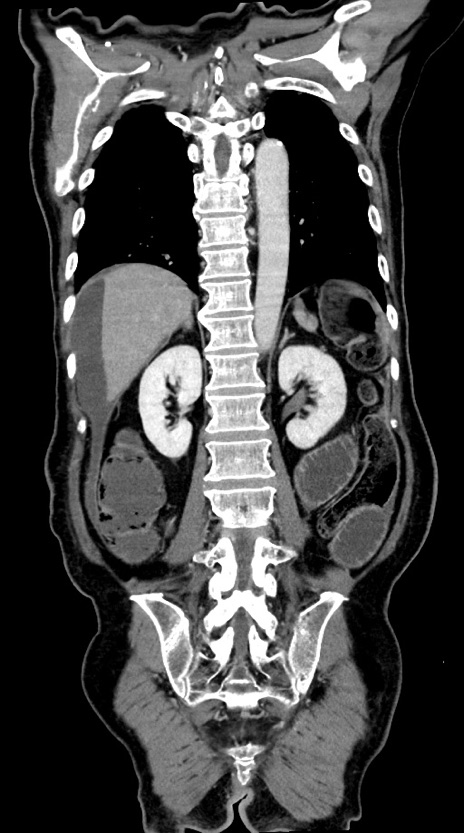

症例28(冠状断像)

【症例】60歳代男性

【現病歴】胃癌にて胃全摘後。食思不振が悪化し、夜中に嘔吐することがある。

【既往歴】胃癌、胃全摘、脾摘、胆摘後

【データ】WBC 5900、CRP 10.56